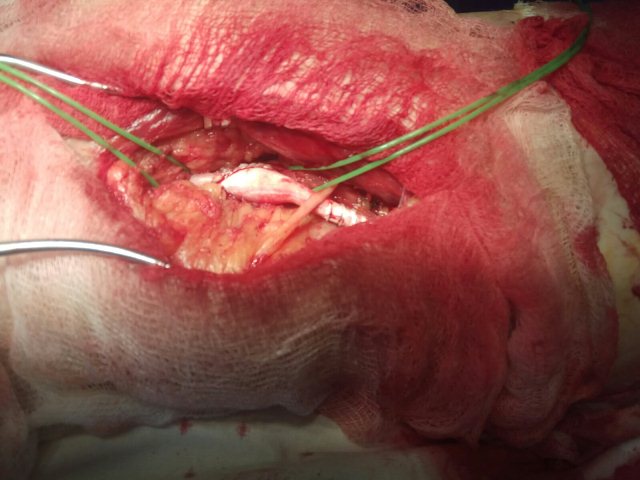

Хирургическая помощь

В ГУ «ЛРКБ» ЛНР ОСХ сотрудниками кафедры госпитальной хирургии и онкологии и врачами ГУ «ЛРКБ» ЛНР ежедневно оказывается специализированная хирургическая помощь больным с атеросклерозом магистральных артерий нижних конечностей.

26.02.2020 производилось плановое оперативное лечение пациенту с многососудистым атеросклеротическим поражением.

03.03.2020 - производилась плановое оперативное лечение пациенту с окклюзией левой поверхностной бедренной артерии.